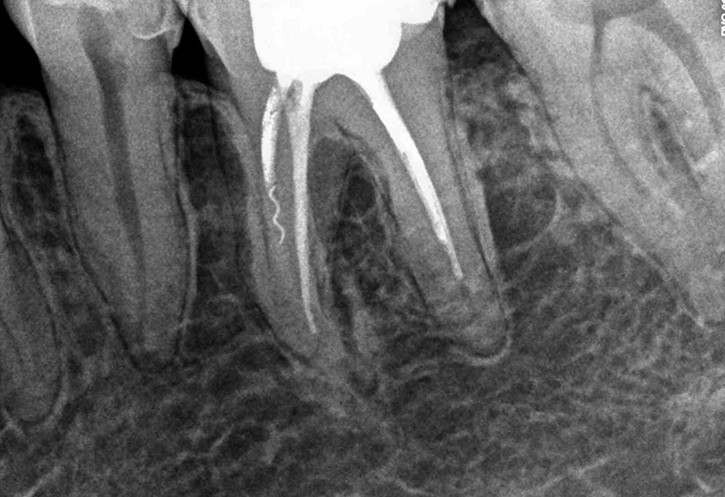

W przypadku zaawansowanych postaci zapaleń miazgi oraz zapalenia tkanek okołowierzchołkowych obraz radiologiczny jest warunkiem rozpoznania. W takiej sytuacji standardem diagnostycznym są zdjęcia przylegające zęba, często wykonywane przy użyciu radiowizjografii na fotelu stomatologicznym w trakcie leczenia zęba. Przydatne jest również badanie RTG OPG pantomograficzne, które pokazuje w dwuwymiarowym obrazie zarówno uzębienie, jak i cały układ kostny szczęki oraz żuchwy.

Główną korzyścią prawidłowo przeprowadzonego leczenia kanałowego jest możliwość zachowania zęba i przywrócenia mu mechanicznej funkcji w jamie ustnej. Prawidłowo udrożnione i poszerzone kanały zęba, które następnie są zdezynfekowane i szczelnie wypełnione, chronią go przed ponownym wnikaniem do nich chorobotwórczych bakterii, powodujących stany zapalne.

Prawidłowo przeprowadzone leczenie kanałowe w wielu przypadkach gwarantuje długotrwałe utrzymanie zęba wraz z jego funkcją. Warunkiem tego jest zachowanie prawidłowej higieny jamy ustnej, dobrej kondycji organizmu oraz regularne wizyty profilaktyczne u stomatologa. By mieć całkowitą pewność uzyskanego efektu leczenia, wymagana jest okresowa kontrola radiologiczna zębów leczonych endodontycznie.

Konieczność powtórnego leczenia endodontycznego może zaistnieć w sytuacji, gdy kanały zęba nie zostały wypełnione do ich anatomicznego wierzchołka lub w trakcie leczenia doszło do złamania i pozostawienia ułamanego narzędzia w świetle kanału korzeniowego. O konieczności powtórnego leczenia endodontycznego może również zadecydować zmiana zapalna przy wierzchołku korzenia, która jest widoczna jedynie na obrazie kontrolnego zdjęcia rtg.